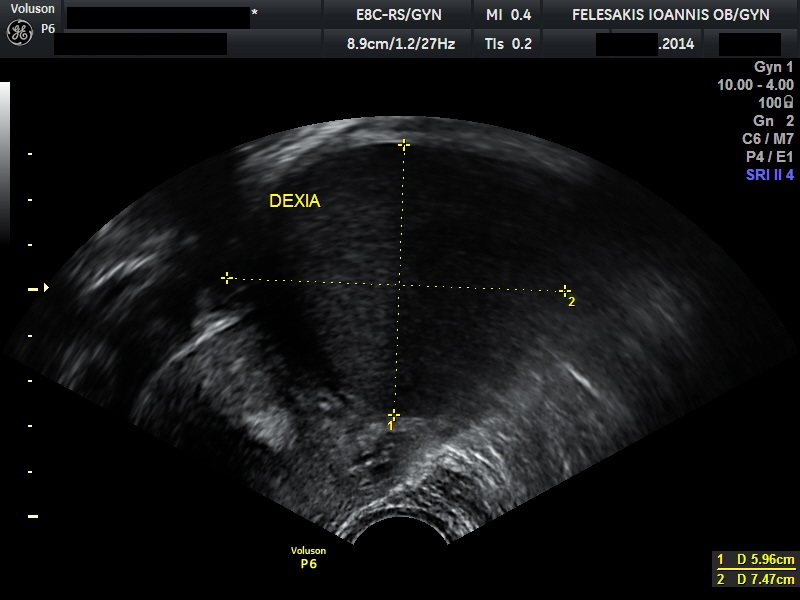

√ Κυστικά μορφώματα ωοθηκών

√ Πολυκυστικές ωοθήκες